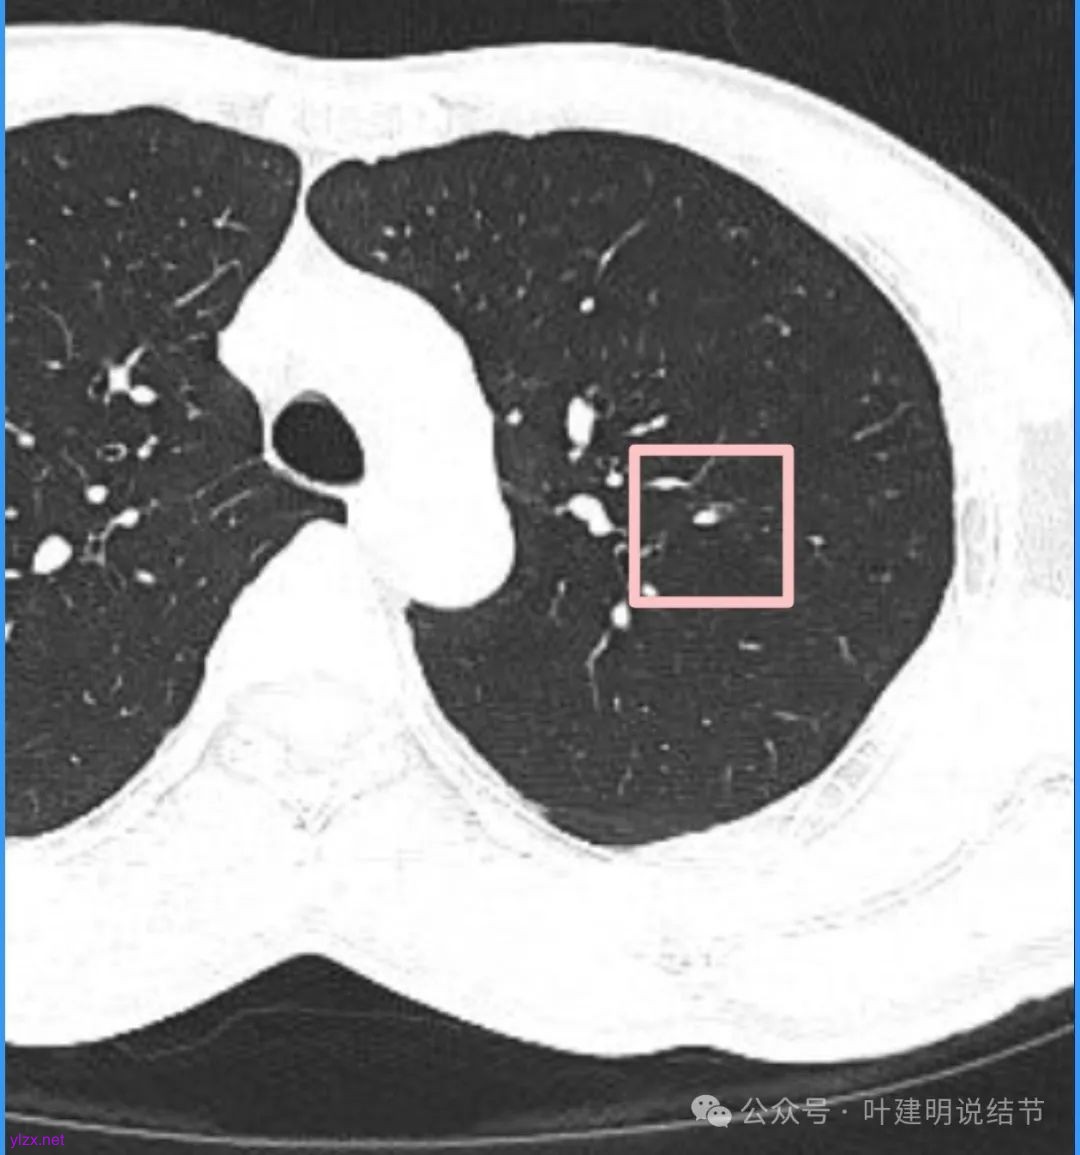

我们先来看2025年3月时的影像:

病灶密度不均,混合密度的样子,相应的细支气管有扭曲略显扩张。

边缘较为毛糙不平,灶内密度杂乱,细支气管穿行,整体轮廓较清。

邻近血管受结节影响,略向病灶侧弯,病灶处是扩张的细支气管还是灶内的空泡征?

有血管征,整体轮廓与边界较清,灶内有蜂窝状。

血管穿过病灶,灶内多个小空泡,整体轮廓较清。

蓝色部分似乎是血管,但似乎又是增厚的支气管壁,局部细支气管扩张。

特别上上图边缘些的层面,蓝色箭头所指的实性明显又像位于扩张细支气管内或与支气管壁一块的样子。